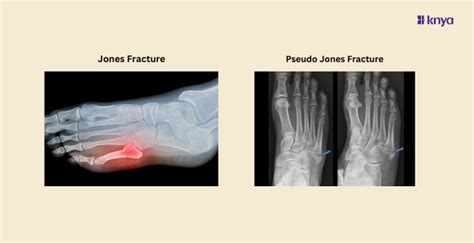

Learn the Difference Between Jones and Pseudo Jones Fracture – Knya